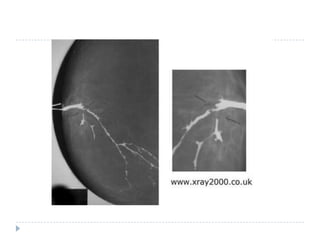

Galaktogrāfija (duktogrāfija)

 K.dz. rtg izmeklēšana ar kontrastvielu. Krūtsgala izvadā

ievada 0,3-1,0ml 60%verografīna vai urografīna;

 Tūlīt pēc ievades veic rtg izmeklēšanu;

 Izvērtē piena vadu formu, kontūras, pildījuma defektus;

 Izmeklējumu veic sievietēm ar aizdomīgiem izdalījumiem

no vienas krūts. Ja ir pienaini izdalījumi no abām krūtīm,

jadomā par endokrīnu patoloģiju.